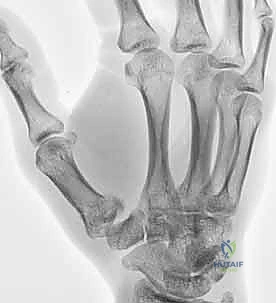

2. التصوير بالأشعة السينية (X-rays)

هي الأداة التشخيصية الأولى والأهم. يتم إجراء صور أشعة بزوايا محددة جداً:

* المنظور الأمامي الخلفي (AP View).

* المنظور الجانبي الحقيقي (True Lateral View): وهو ضروري جداً لتقييم مدى الخلع أو الانزياح في المفصل.

* منظور روبرت (Robert's View): وضعية خاصة للأشعة السينية تظهر مفصل الإبهام الرسغي السنعي بوضوح تام وتكشف عن أدق التفاصيل في كسور بينيت ورولاندو.